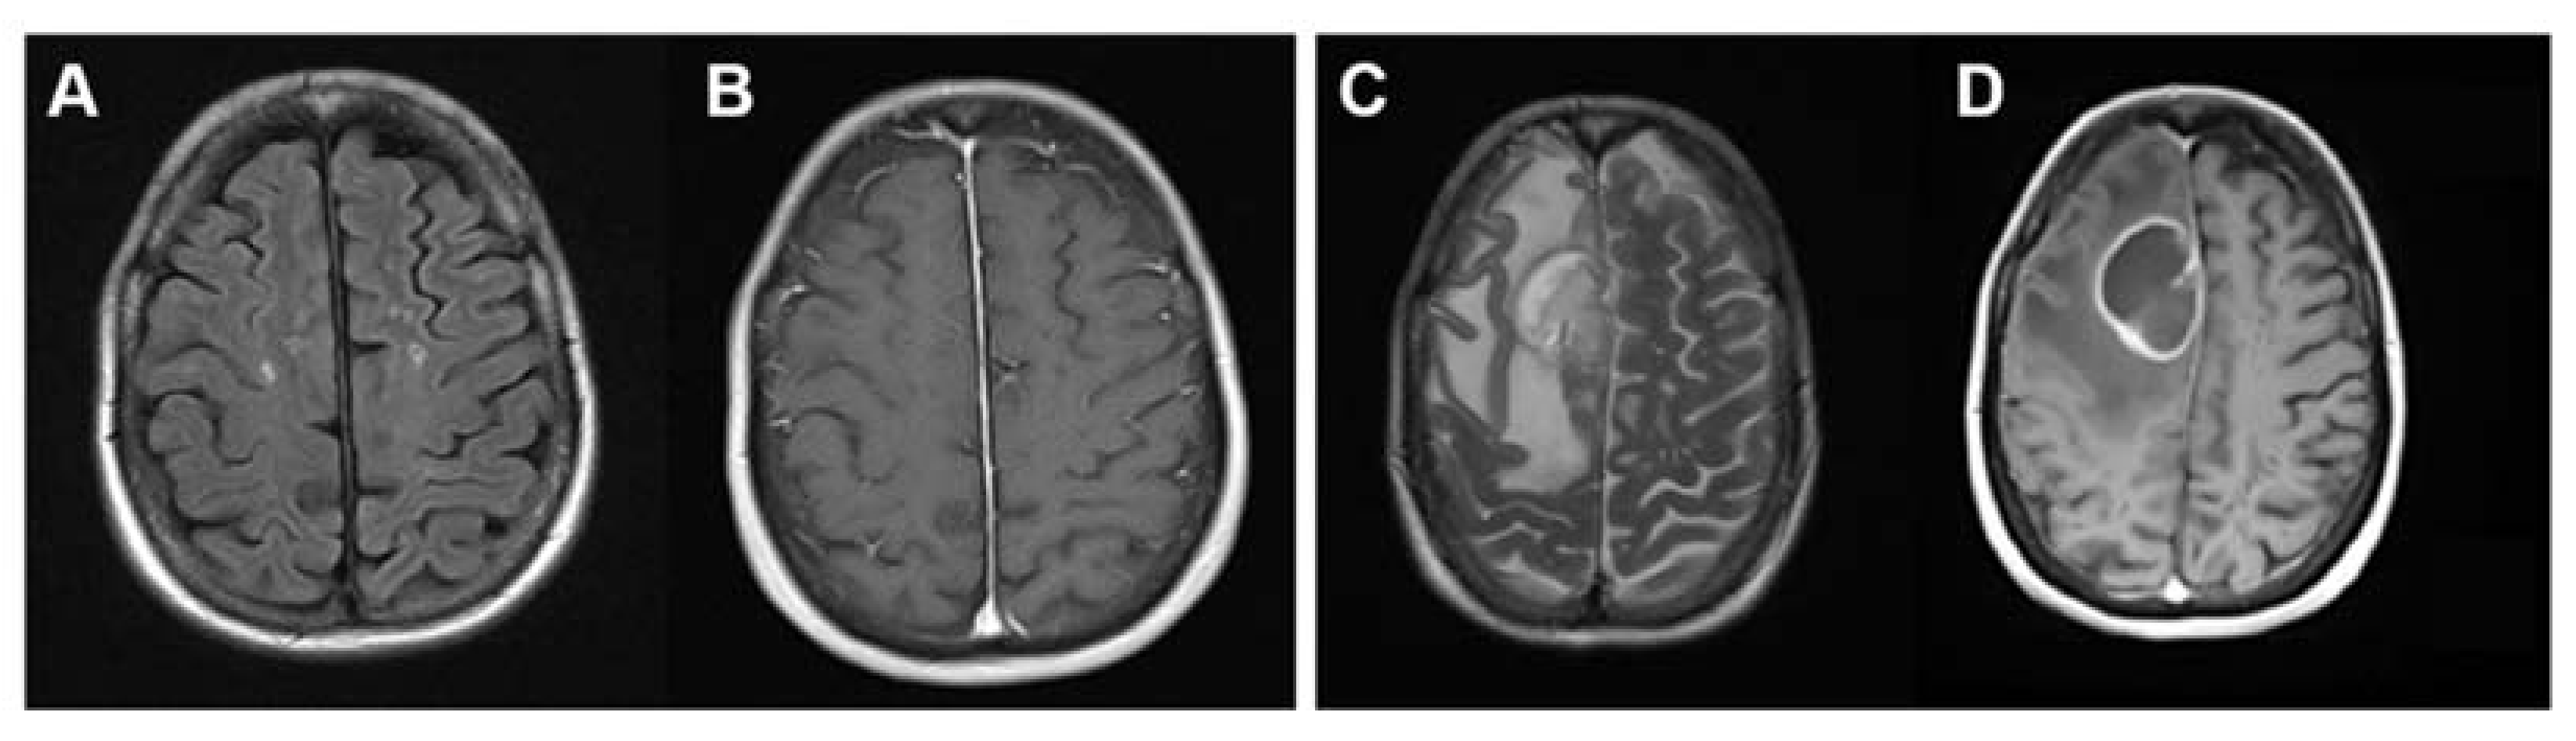

2. Case Report